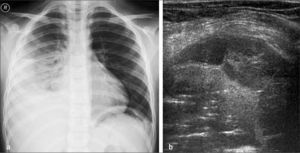

b)Empiema pleuralEn algunos casos de neumonías con derrame se observa extensión de la infección al espacio pleural, con formación de fibrina y exudado purulento que determina la aparición de septos y lóculos en el espesor del líquido pleural.

Puede sospecharse en Rx simple, cuando el compromiso pleural no pre senta el aspecto descrito previamente para el derrame libre, especialmente si se observa un aspecto convexo localizado que sugiere loculación. En estos casos el estudio puede complementarse con US efectuada con transductor de alta resolución. Ramnath (11) clasificó los derrames en “bajo grado” cuando están constituidos por líquido anecogénico (Figura 9), sin septos y “alto grado” cuando muestran imágenes de septos, lóculos o sedimento, signos altamente sugerentes de derrame pleural complicado (Figura 10).